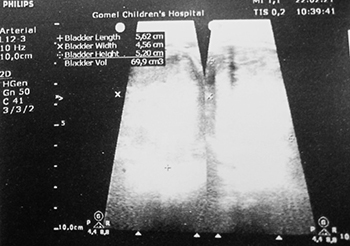

УЗИ почек и надпочечников: УЗ-картина объемного образования мочевого пузыря, забрюшинного пространства (гематома (?) опухоль (?) абсцесс (?)) (см. рис. 2);

Рисунок 2. Результаты УЗИ почек и надпочечников.